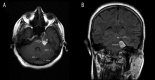

Case report: In this report we describe a patient complaining of vertigo caused by spontaneous rupture of dermoid cyst, preoperatively diagnosed by CT and MRI. Cranial CT revealed a dense fatty lesion adjacent to the posterolateral parasellar region on the left with multiple small, dense fat droplets scattered in the subarachnoid space corresponding to a dermoid cyst rupture. Cranial MRI sections revealed a lesion with mixed-signal-intensity and multiple hyperintense droplets scattered through the cerebellar surface on the left. No enhancement was found on axial T1-weighted MRI after intravenous Gadolinium administration. Diffusion weighted image (DWI) and apparent diffusion coefficient map studies exhibited explicit restricted diffusion.